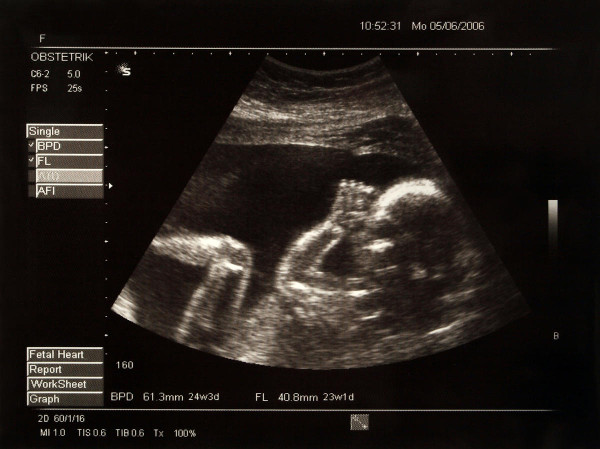

A typical echography is shown below.

With the refinement of imagine techniques, ultrasounds could be used for echographies. As the waves hit the internal tissues and bounce back from them, they are not deemed completely safe, but mostly they are not harmful, if used wisely.